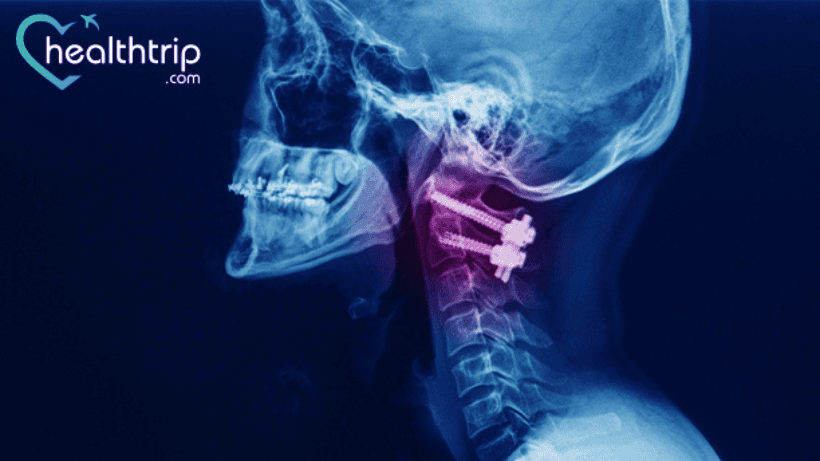

One such commonly performed spinal fusion surgery is Anterior Cervical Discectomy and Fusion Surgery(ACDF).

In these cases, more surgery was required to fix such issues. The patients underwent a successful atlantoaxial and C2-C3 fixation, and they were able to walk independently again 21 months after the new surgery.